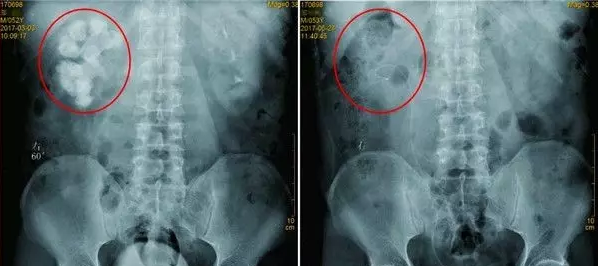

四川结石病医院接诊了一名52岁的肾结石患者,他体内的结石已经占满了整个右肾,成为了一个“老姜”;状的结石,而这名患者跟医生透露说:20年内,他竟接受了200多次体外碎石!结果结石越来越多越来越大,终于四川结石病医院专家将患者肾脏的结石全部拿下。>>>为什么200次没有碎下来?